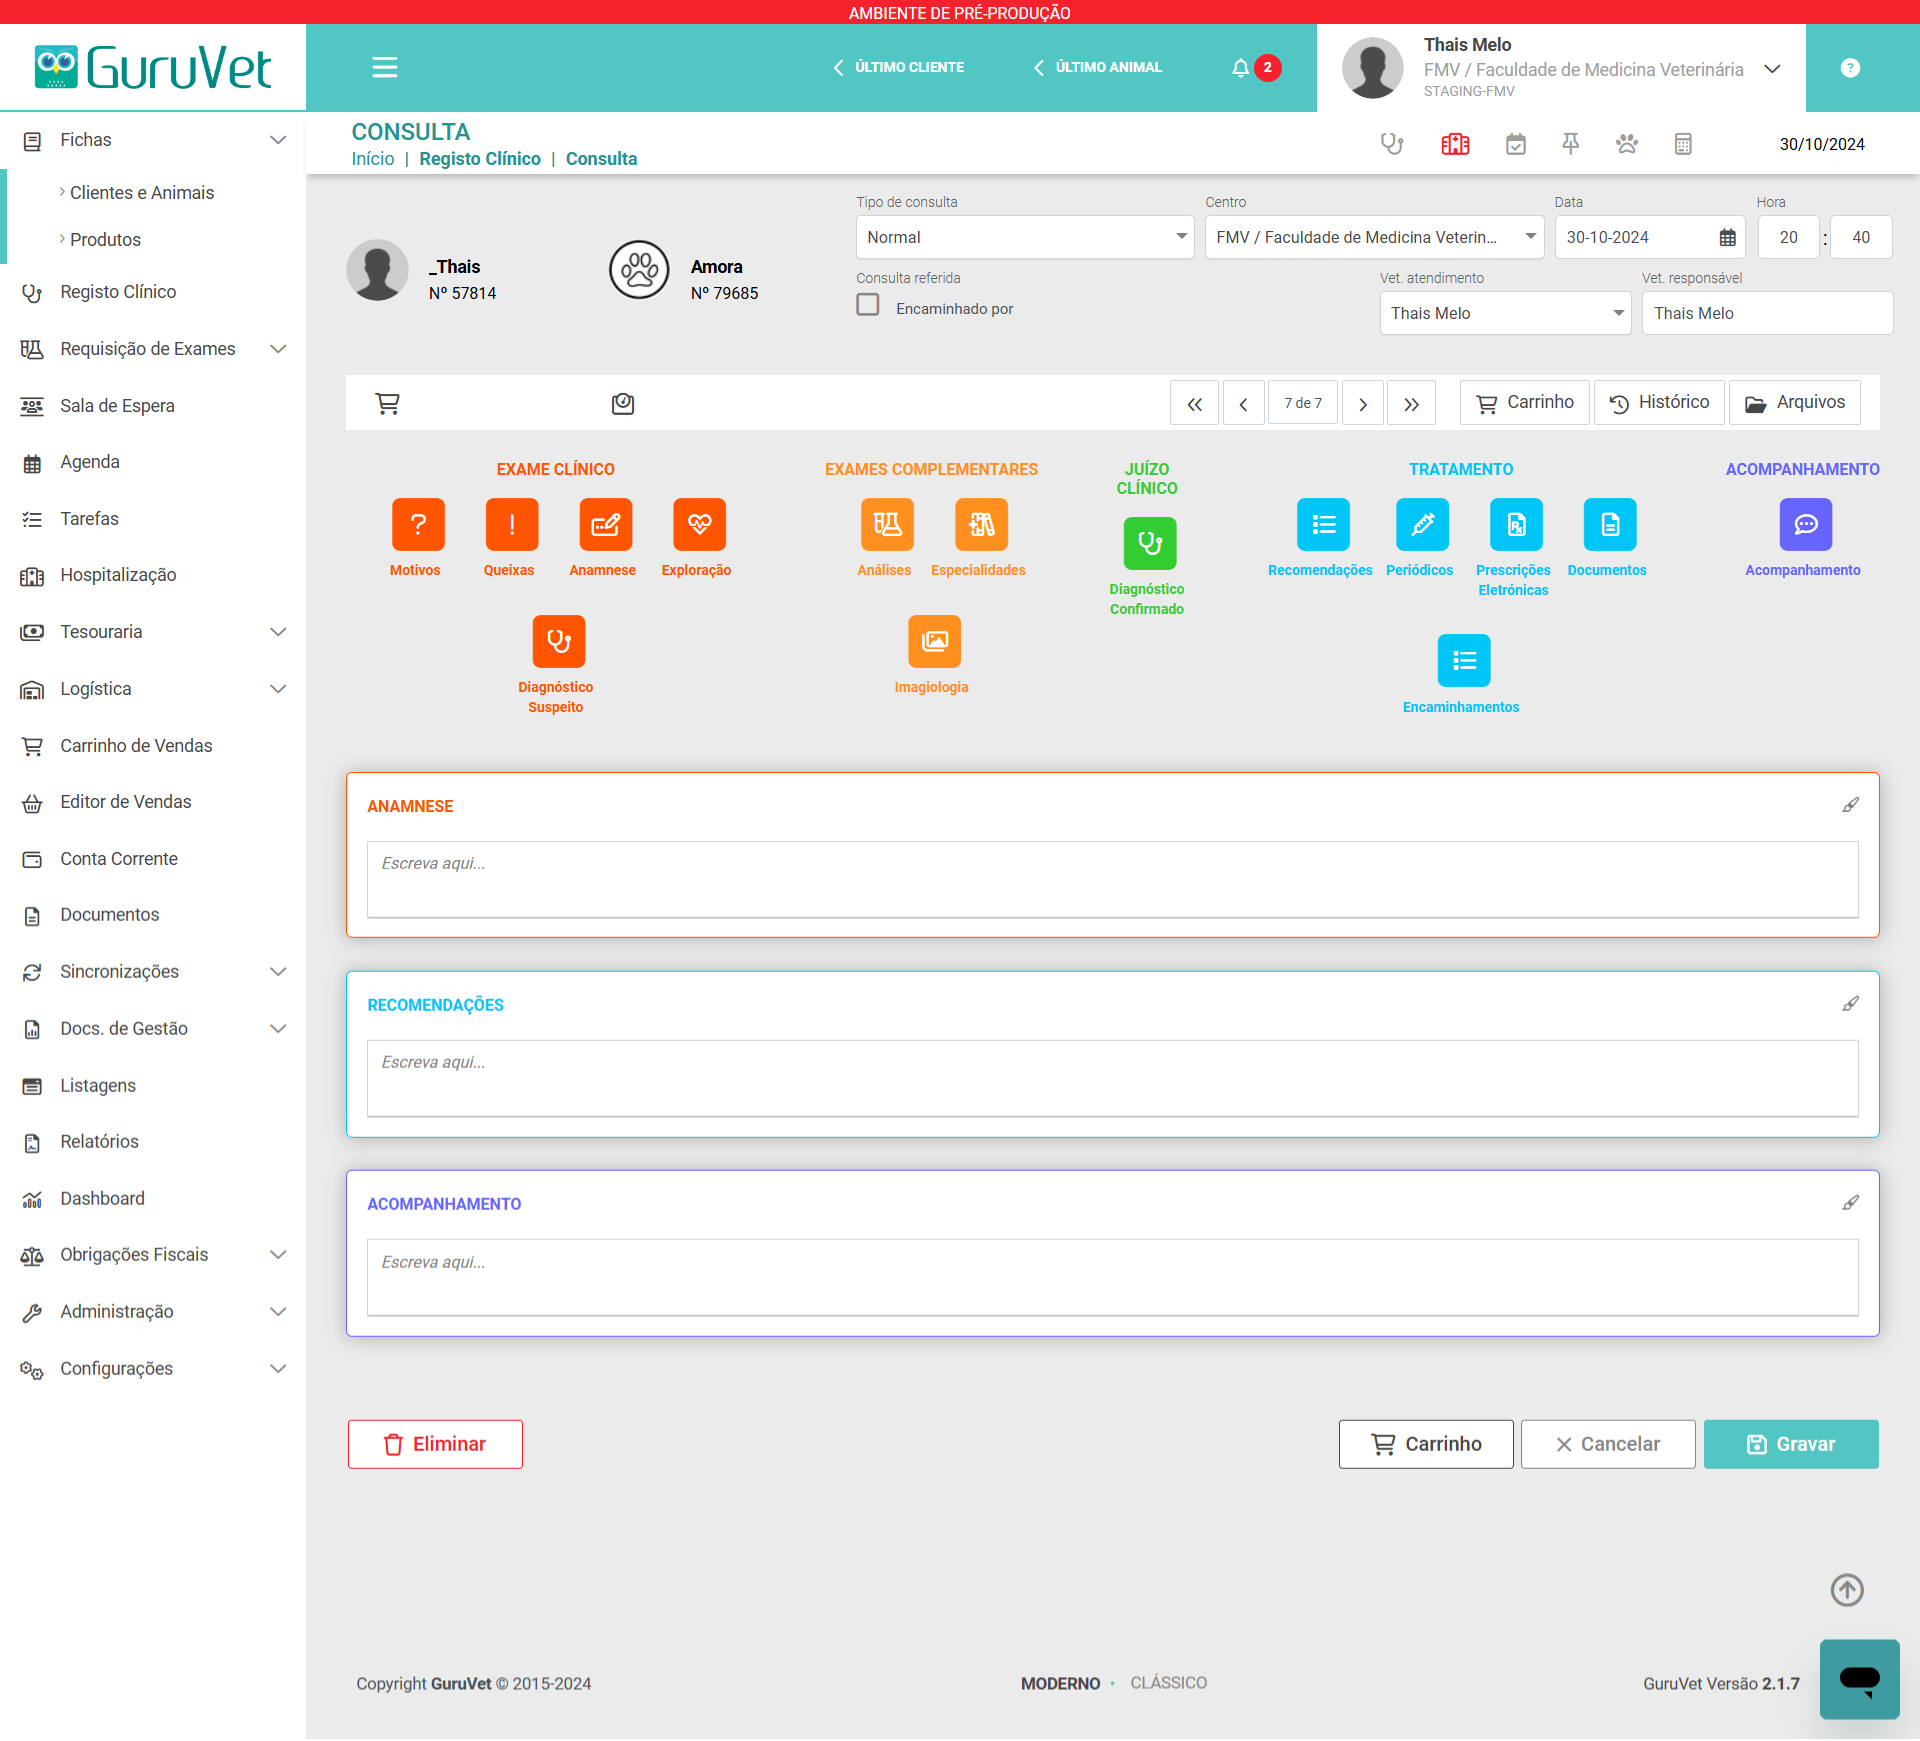

PRODUTO

GuruVet - Software de Gestão para Clínicas e Centros Veterinários

O GuruVet é um sistema para clínicas veterinárias desenvolvido para ser o mais completo, intuitivo e fácil de utilizar possível, de forma a apoiar o veterinário e a sua equipa. Para criar o GuruVet, reunimos especialistas de várias áreas (administrativa, jurídica, contabilística, veterinária e tecnológica) para estudar o funcionamento dos centros veterinários e desenhar os processos de acordo com as boas práticas de gestão.